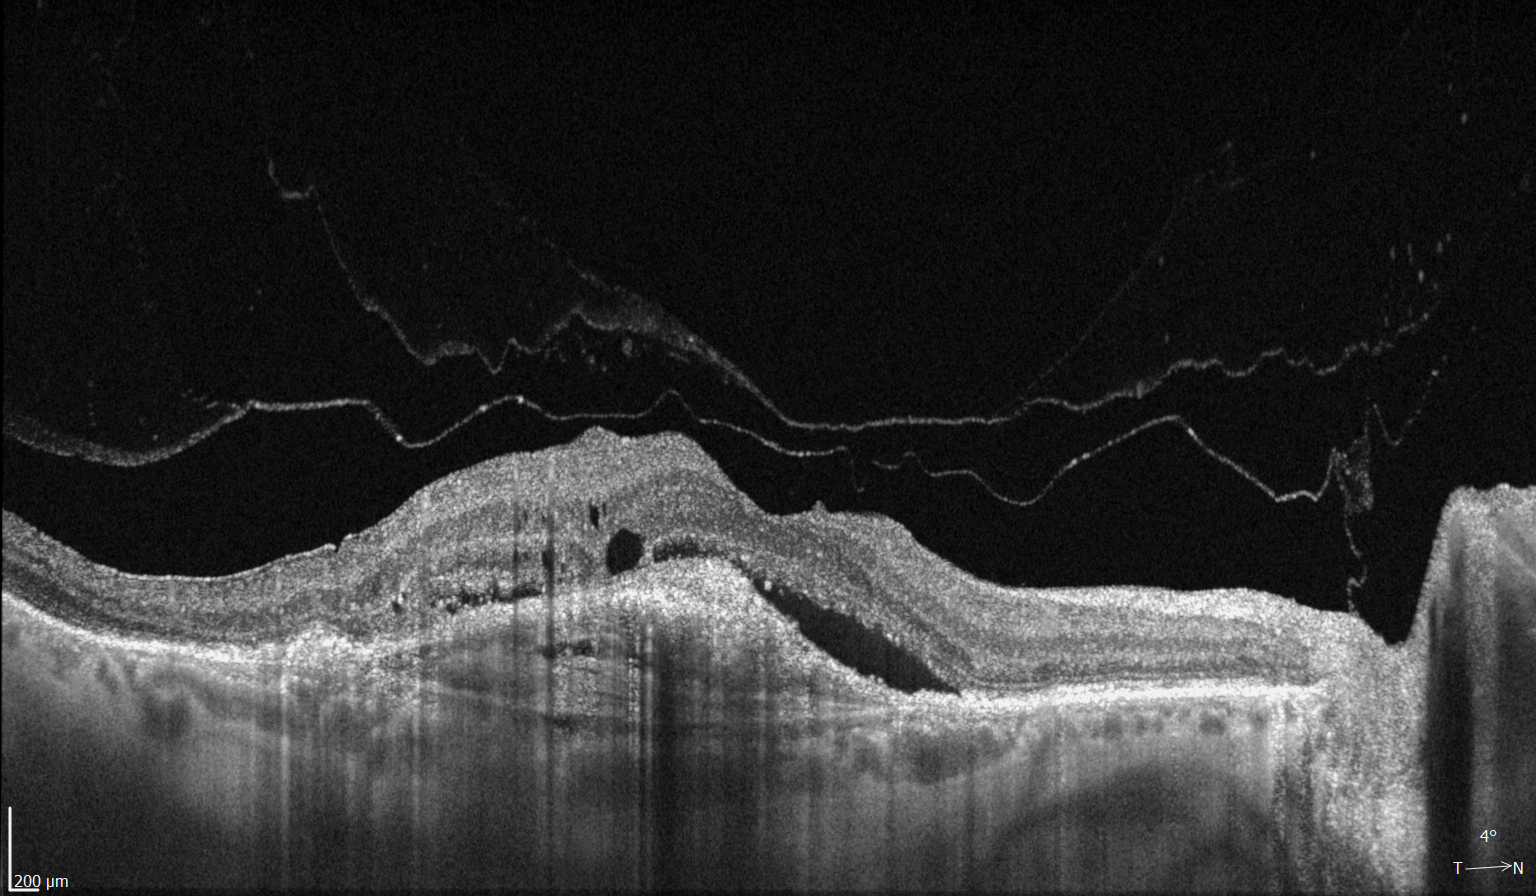

Диагностика зрения: Когерентная томография сетчатки